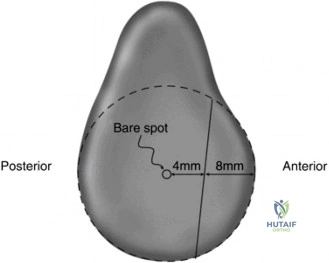

The concept of the Glenoid Track is essential for understanding bipolar bone loss. The glenoid track is the contact zone of the glenoid on the posterior humeral head as the arm moves through its range of motion. If a Hill-Sachs lesion extends medial to the glenoid track, it is classified as "off track" and will engage the anterior glenoid rim, levering the humeral head out of the joint. Glenoid bone loss narrows the glenoid track, making a previously "on track" Hill-Sachs lesion "off track."

The en face view of the glenoid on 3D CT with the humeral head digitally subtracted allows for precise measurement. The "best fit circle" method is commonly utilized. A circle is drawn matching the contour of the inferior and posterior glenoid, and the area or width of the missing anterior bone is calculated relative to the area or diameter of the circle. The Pico method compares the surface area of the injured glenoid to the contralateral normal glenoid, assuming the contralateral shoulder is uninjured. The humeral head must also be evaluated to calculate the glenoid track, measuring the width of the Hill-Sachs lesion and the intact anterior glenoid bone bridge.

The Glenoid Track concept, detailed by Di Giacomo, Itoi, and Burkhart in 2014, revolutionized the understanding of bipolar bone loss. They provided a biomechanical framework to determine whether a Hill-Sachs lesion would engage the anterior glenoid rim based on the width of the intact glenoid. This concept shifted the focus from isolated glenoid or humeral defects to the dynamic interplay between the two surfaces, guiding the use of the remplissage procedure for off track lesions with subcritical glenoid bone loss.